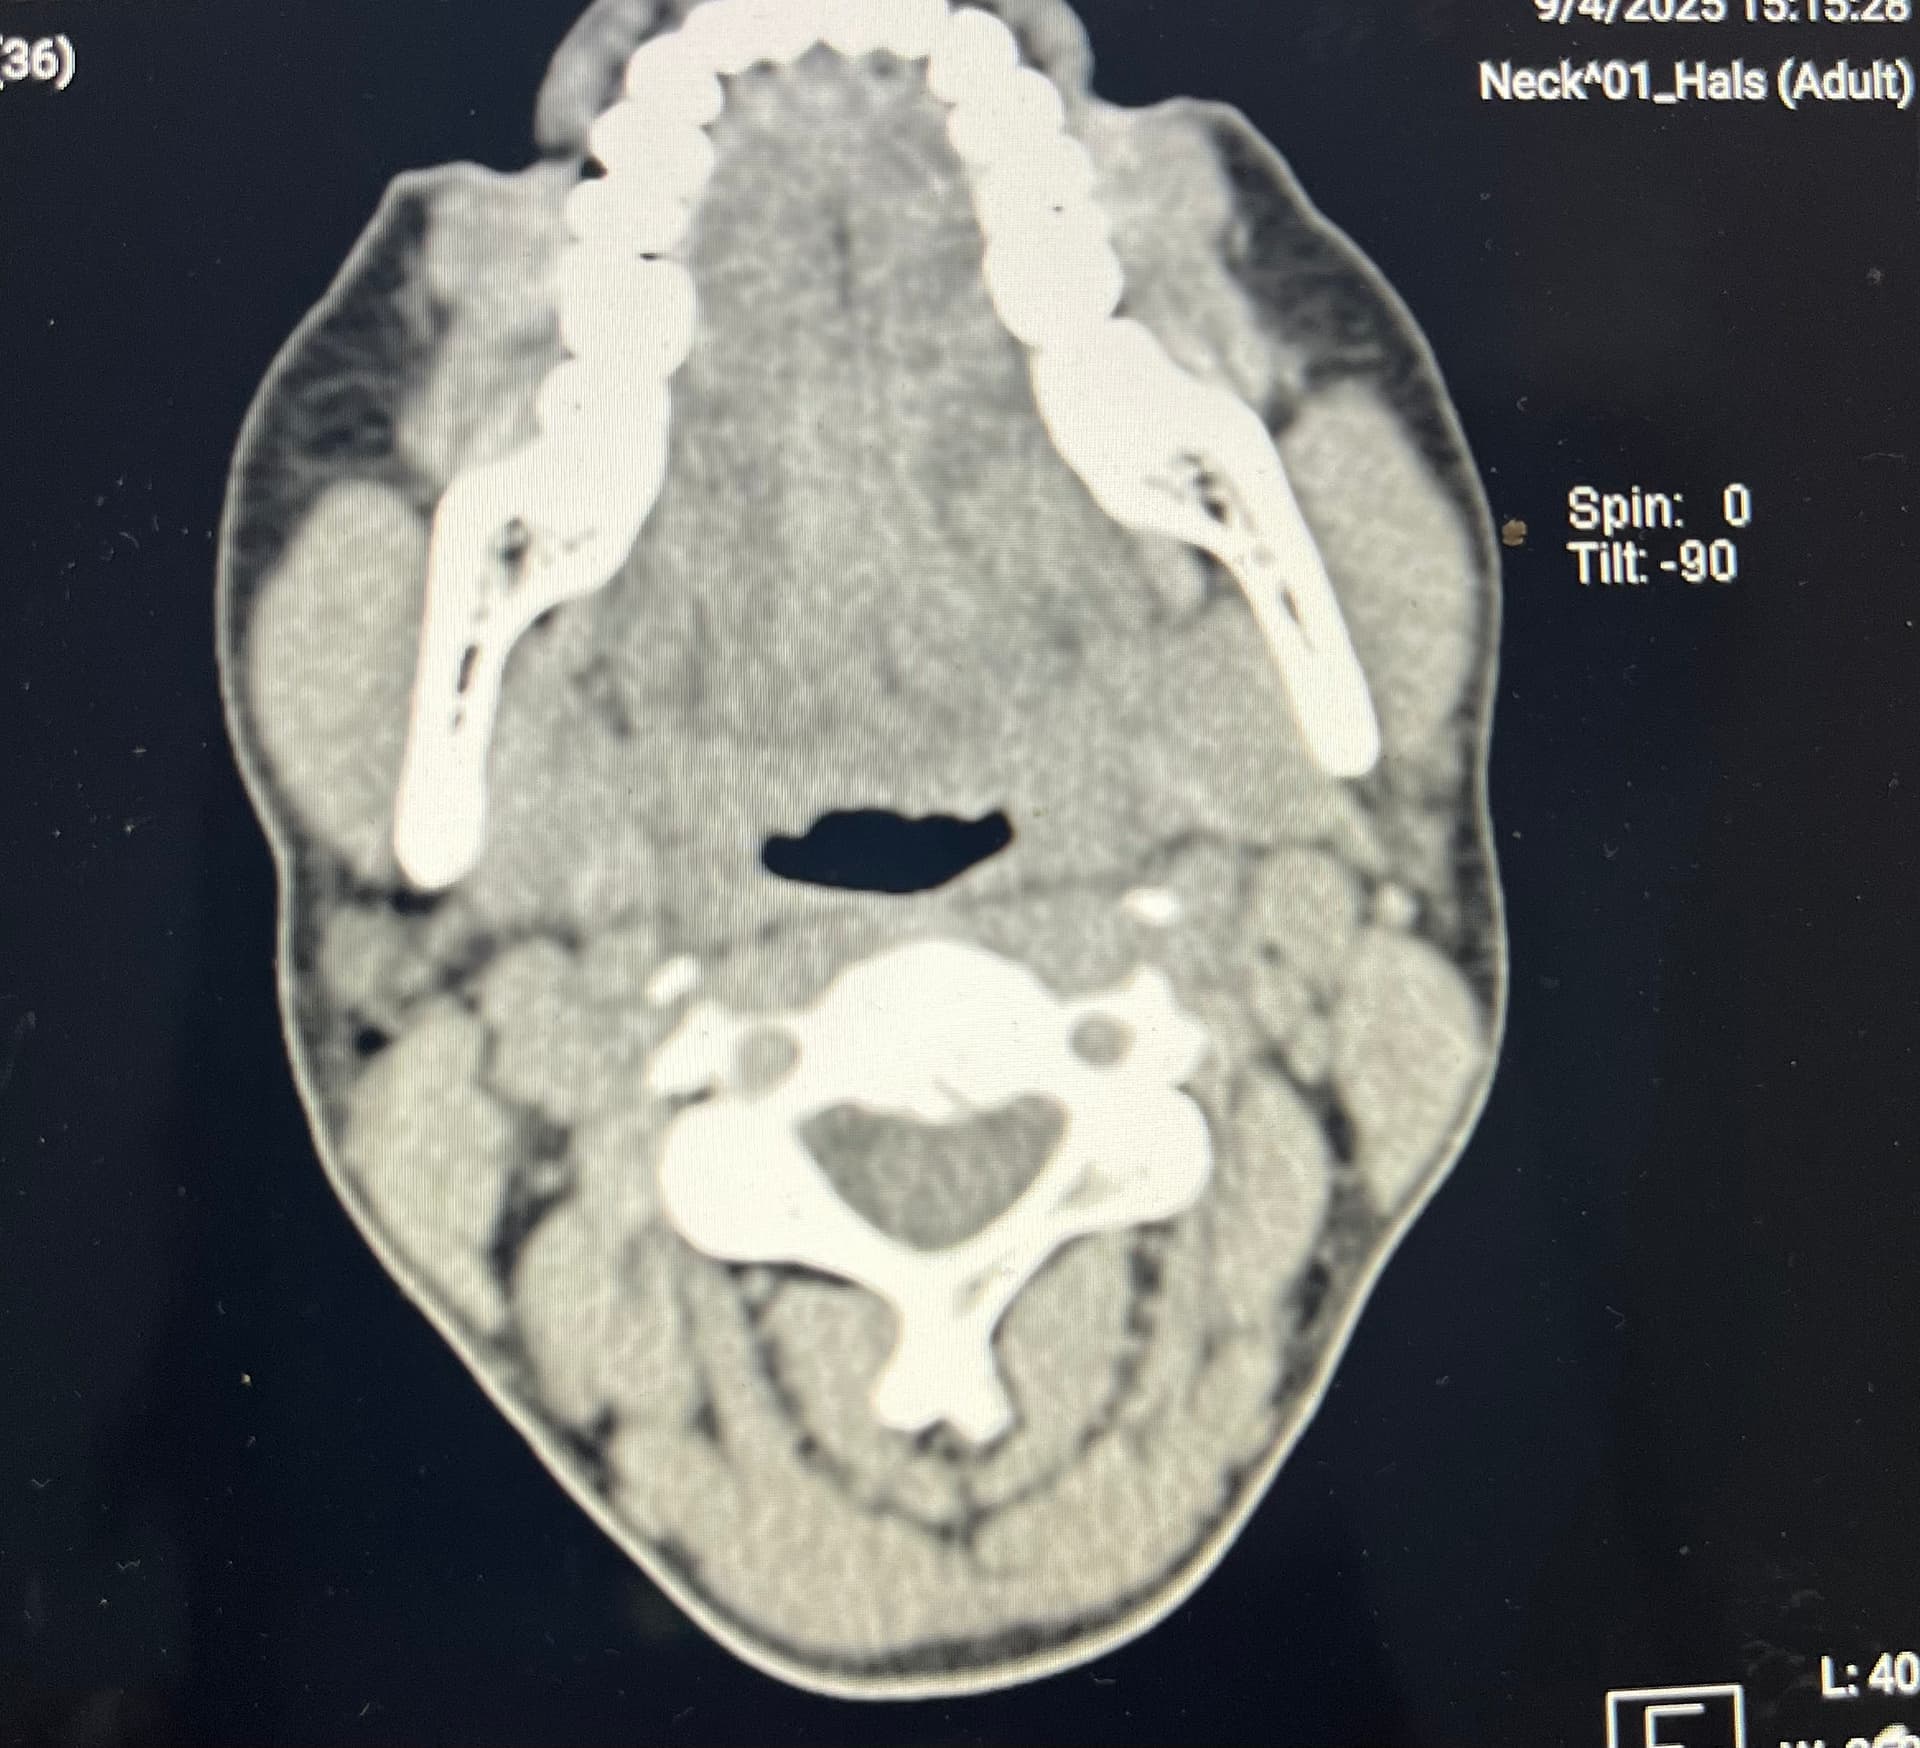

Over the years I have had many mri’s and ct scans trying to understand, the most recent with contrast. Last year a doctor brought up eagle syndrome and I sure hope to have an answer soon. My next dr apmt isn’t for awhile so I was hoping someone might be able to help me understand my images to see if it could be eagle syndrome. 2 doctors said it might be but that it would be bilateral so thats unlikley. I really appreciate any help!!

@Coco1 - Welcome to our forum! I’m sorry you’re having so much pain, & that it’s been going on for so long. Bilateral ES is not uncommon. Many of our forum members have or had bilateral ES. The symptoms you listed are consistent with symptoms we know can be caused by ES, & after looking at your images, it looks possible that your stylohyoid ligament(s) & possibly hyoid bone are the cause of yours. The pain you have is caused by nerves in your neck. Swollen lymph nodes & a very sore throat can also go along w/ ES. If the styloids are very curved, they can poke into the tonsil area in the throat so that could be why you’re feeling pain in your tonsil area. I had pain under my left jaw & could actually feel my styloid under there. It was a hard lump, & I thought it was an inflamed lymph node or salivary gland.

The first picture you posted is the best. Do you have a similar picture of the other side? I can’t really see anything helpful in the 2nd & 3rd pictures.

What I noticed is your styloid doesn’t look very long but you have a calcified section of stylohyoid ligament which is pretty thick so that could be contributing to your symptoms. The greater horn(s) of your hyoid bone also look quite long, nearly touching your spine. They can also cause symptoms when they are too long (Hyoid Bone Syndrome). The last observation is that you appear to have significant forward head posture which is caused by your cervical spine straightening out. It has lost its natural lordotic curve. When the cervical curve is gone, the styloids & stylohyoid ligaments, if calcified, sit much closer to the nerves & vascular tissues in the neck & are much more likely to cause ES symptoms.

I annotated your first image to show you the styloid, stylohyoid ligament, & greater horn of your hyoid that could all be contributing to your symptoms. You can see how straight your cervical vertebra are in that picture.

I agree with everything that @Isaiah_40_31 has said, she’s covered it all as usual! Looking at the new image you posted, the styloid & calcified ligament look longer, & it also looks like there’s not that much of a gap between it & the C1 process, which can cause symptoms as blood vessels & nerves can get compressed between the two, although it may just be the angle… It’s certainly worth seeing someone with experience with ES if you’re able!

It might also be worth asking your doctor if your thyroid cartilage is normal, as it looks quite calcified too, but might be wrong about that…

@Coco1 - I agree w/ @Jules about the thyroid cartilage, too, but I’ve seen some similar thyroid cartilage images & was told they were normal. It’s worth asking about though.